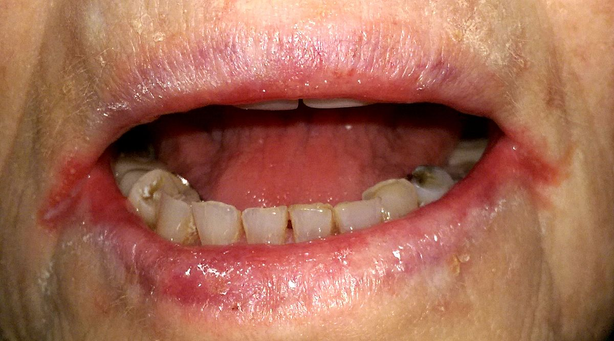

17. A 6-month-old infant girl is brought to the pediatrician for evaluation of impaired vision. The patient was born at home via an uncomplicated vaginal delivery but did not receive any postpartum medical evaluation, with the parent stating they wanted a “natural” birth. According to her parents, the patient “tends to stare at the wall, even if cartoons are playing on the television.” The patient also does not smile when the parents are playing with the patient. The patient is at the 10th percentile for length and 5th percentile for weight. Vitals are within normal limits. Physical examination reveals the findings shown below. No hepatomegaly or jaundice is observed. Urine dipstick testing is normal. Further testing reveals the presence of reducing substances within the urine. Which of the following best describes the pathophysiology behind this patient’s visual symptoms?

Image reproduced from Wikimedia Commons